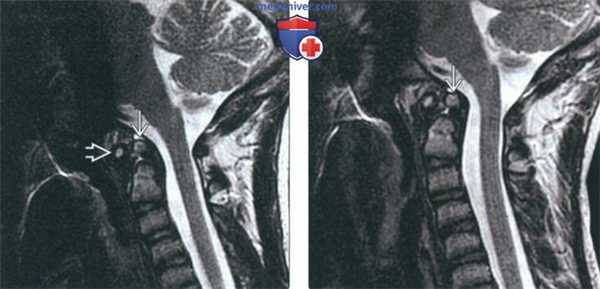

(Слева) На сагиттальной МРТ (Т2 ВИ) в положении сгибания определяется переднее положение дистопической зубовидной костив относительно С2. Расстояние между передней дугой С1 и зубовидной костью сохранено; определяется нарушение положения зубовидной кош относительно С2 по сравнению с изображениями в нейтральном положении и при разгибании (атланто-аксиальная нестабильность).

(Справа) На сагиттальной MPT (Т2 ВИ) в положении разгибания у этого же пациента положение зубовидной кости обычное. На сагиттальной МРТ (Т2 ВИ) в положении сгибания определялось переднее смещение зубовидной кости, свидетельствующее об атланто-аксиальной нестабильности.

(Слева) На сагиттальном Т2-ВИ, полученном в положении сгибания, видна расположенная несколько кпереди относительно С2 дистопичная зубовидная кость. Сохраняется нормальное расстояние между передней дугой С1 и костью, однако отмечается изменение положения кости относительно С2 (атлантоаксиальная нестабильность) по сравнению с изображениями в нейтральном положении и положении разгибания.

(Справа) Это сагиттальное Т2-ВИ получено в положении разгибания и отражает нормальное расположение зубовидной кости. В положении сгибания эта кость смещается кпереди, что свидетельствует об атлантоаксиальной нестабильности. (Слева) КТ шейного отдела позвоночника, сагиттальный срез: врожденное сращение передней дуги С1 и крупной зубовидной костив. Нормальные взаимоотношения между скатом В и зубовидной костью сохранены. Субаксиальные сегменты шейного отдела позвоночника во всех отношениях нормальны, признаков каких-либо других аномалий сегментации не выявлено.